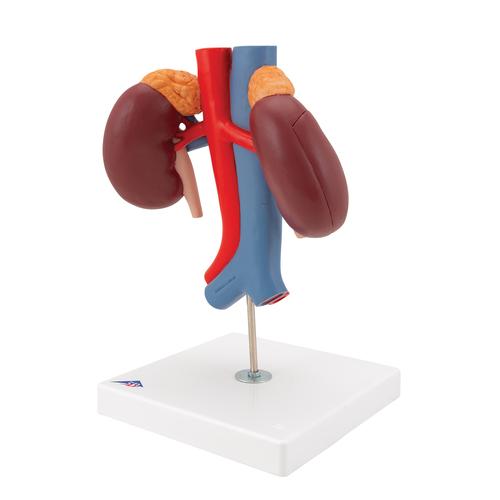

Эта модель в натуральную величину демонстрирует почки с надпочечниками, мочеточники, внутрипочечные сосуды и крупные кровеносные сосуды, расположенные в непосредственной близости от почек. Съемная передняя половина правой почки позволяет увидеть почечную лоханку, чашечки, корковый и мозговой слои почки. На подставке.